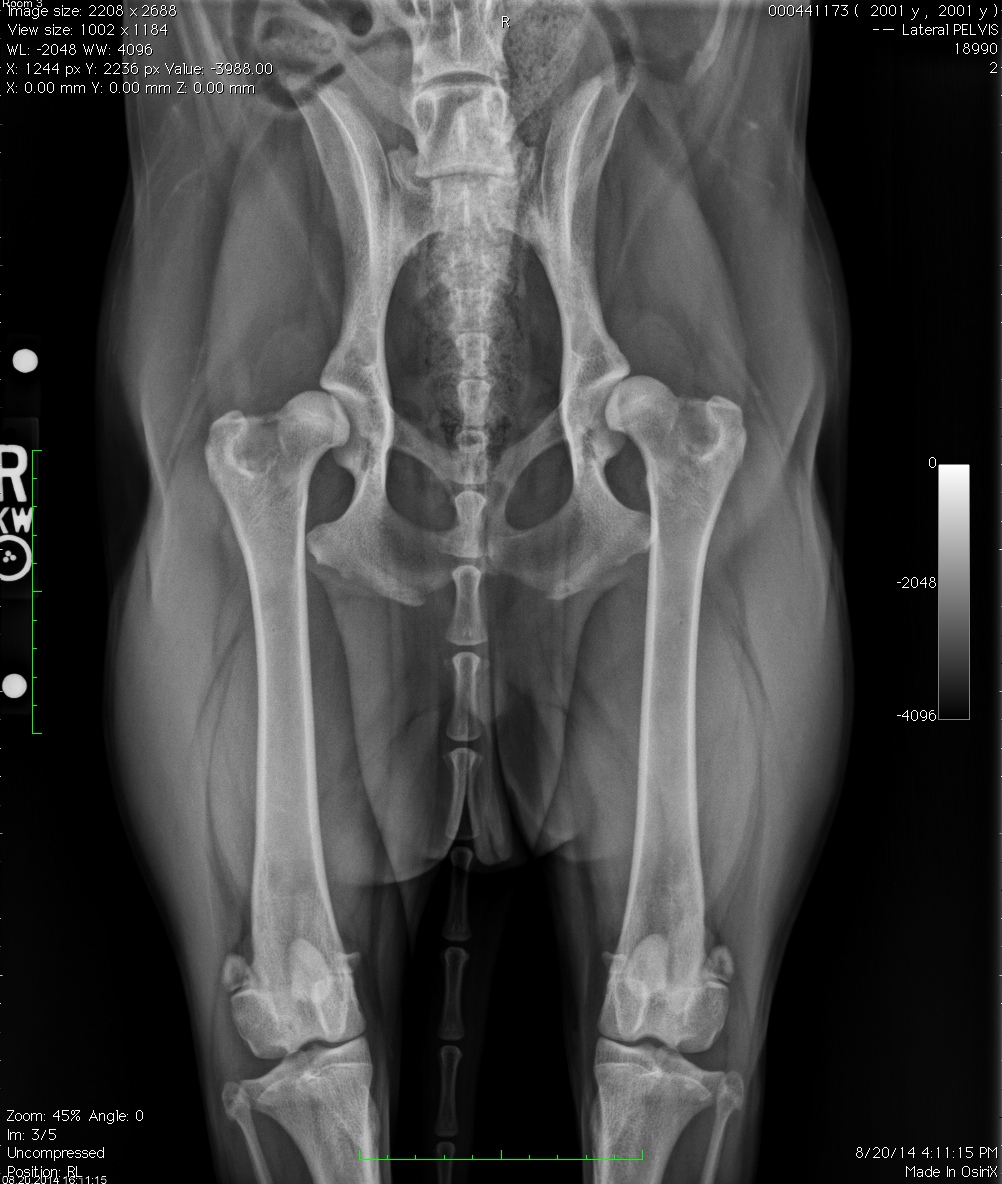

Frankie pre-operative radiographs Published November 28, 2015 at 1002 × 1184 in When to Consider a Total Hip Replacement??? ← Previous Next → Frankie’s pre-operative x-rays. Bilateral hip dysplasia. Share this: Share on X (Opens in new window) X Share on Facebook (Opens in new window) Facebook Email a link to a friend (Opens in new window) Email Print (Opens in new window) Print Like Loading...